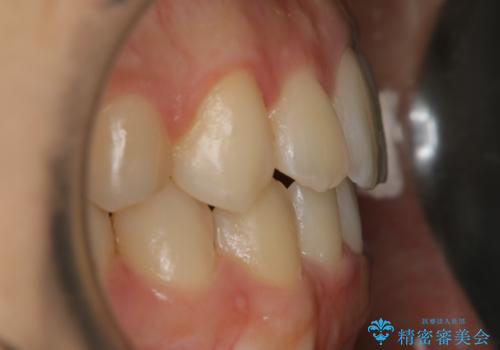

【非抜歯】すきっ歯と噛み合わせの治療

- 上の前歯のすきっ歯と下の前歯のガタつきを主訴にご来院されました。

噛み合わせの改善も同時に進めつつ、主訴の部分も効率的に治していくためマウスピース装置でゴムかけを行いながら治療を進めていきました。

正中離開(すきっ歯)

真ん中の歯が左右に開いてしまい隙間ができてしまう状態を「正中離開」といい、俗にすきっ歯と呼ばれています。

隙間を埋めていく方向に歯を移動させることで改善していくケースが多く、比較的治りやすい不正咬合のひとつとされています。

しかしながら、歯が捻じれていたり、噛み合う歯との位置関係によっては治療が難しくなる場合があります。